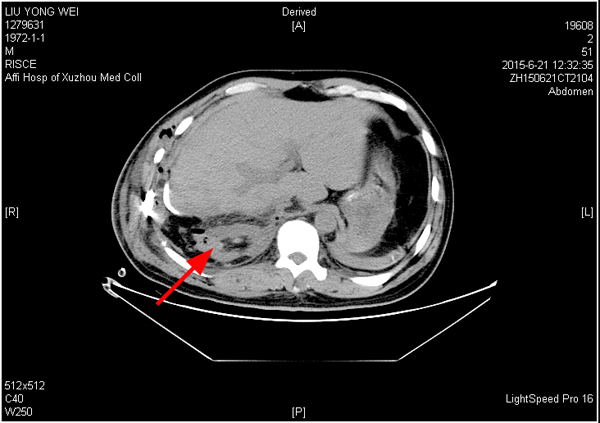

3、術(shù)后分別于2015年6月21日(術(shù)后第1天)和6月25日(術(shù)后第5天)的2次CT復(fù)查均顯示該患者的右腎存在。(圖一、圖二)

圖一 2015年6月21日(術(shù)后第1天)CT,右腎如箭頭所示。